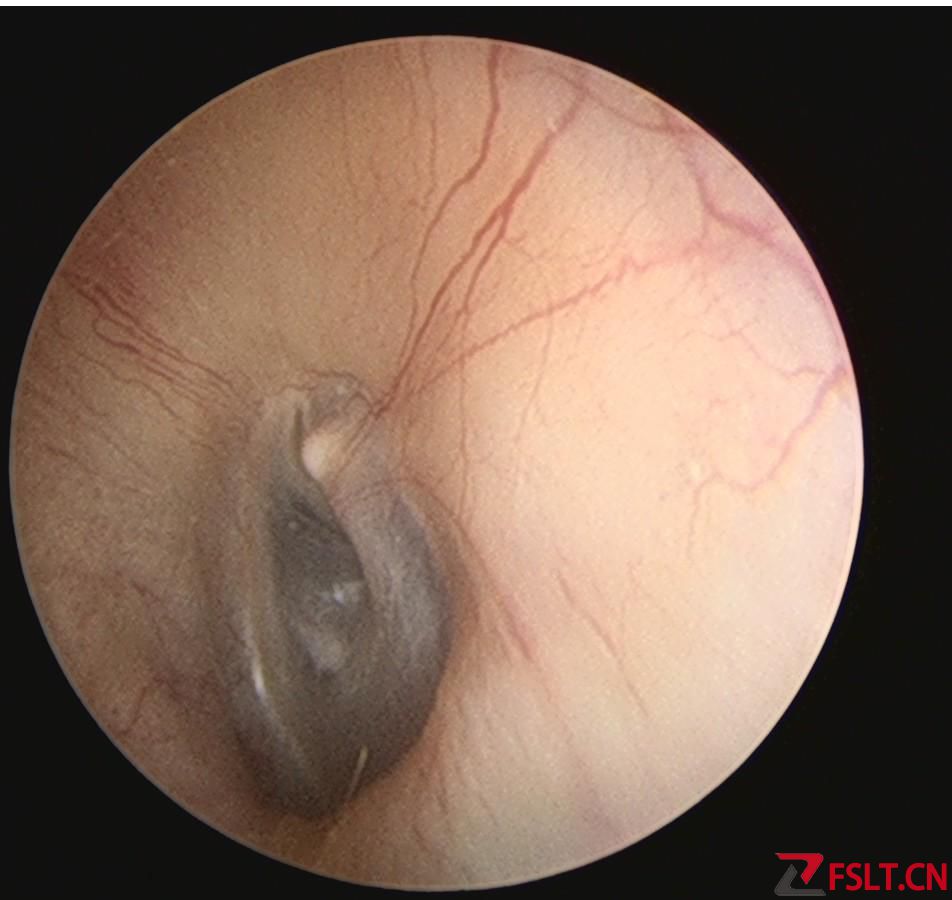

手术由梅晓峰主任和郑立岗主任主刀,这次做的是全麻内淋巴囊减压手术,在耳后做切口后暴露乳突骨皮质,打开乳突腔,暴露后半规管和内淋巴囊,切开内淋巴囊放置引流装置。缝合切口并放置负压引流。整个的手术用时约2个小时,非常顺利。术后第二天查房患者无明显的不适,无手术相关的并发症。自觉耳鸣消失,听力较术前稍有提高,无眩晕发作。